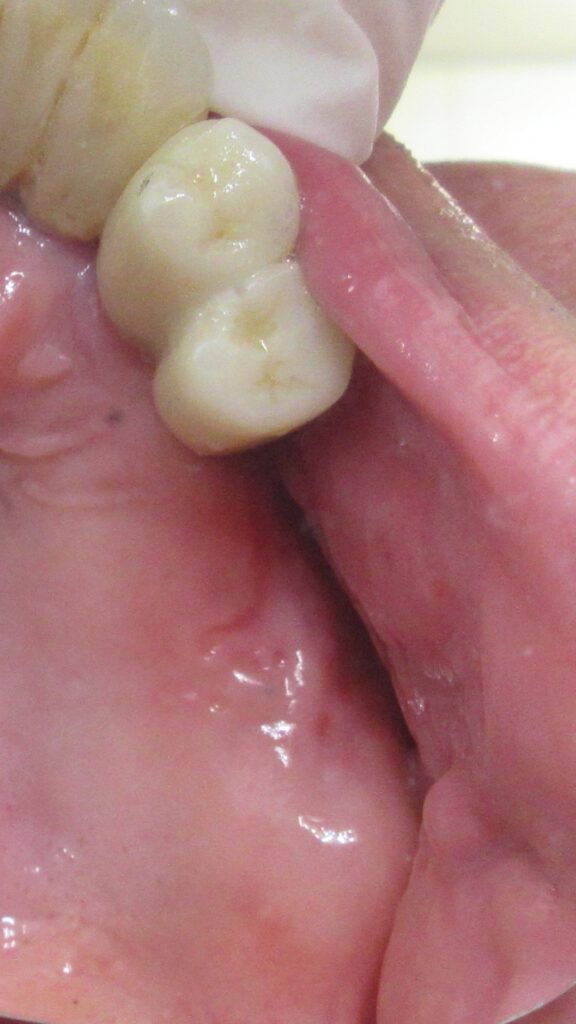

今回の患者様はインプラント植立を希望され、左上6番目・7番目の2本の植立が決まりました。

まずは左上6番目の歯茎から骨の部分までを穴開けパンチの要領で穴を開けていきます。

くりぬいた部分の歯肉を取り除き、次は骨に穴を開けていきます。